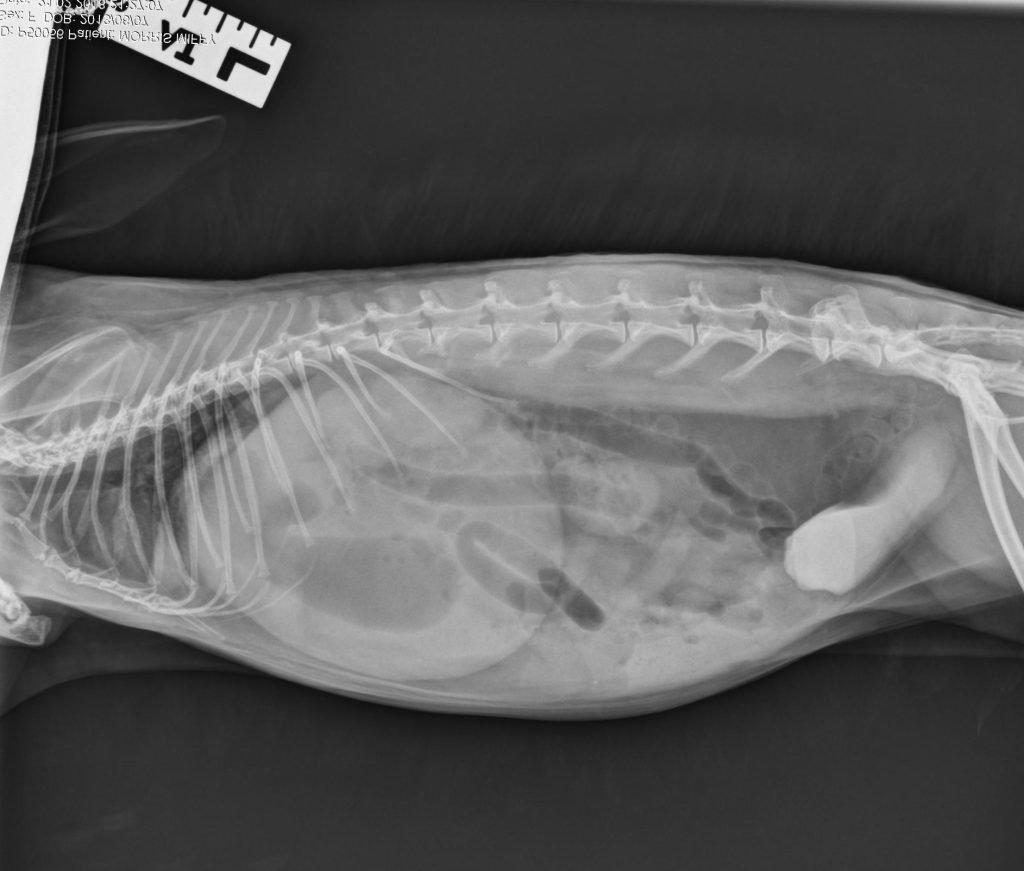

Attached is a radiograph of a rabbit with limited opportunity to exercise due to hutch confinement. Yes, that is a large amount of calcium sludge in the bladder, not contrast material!